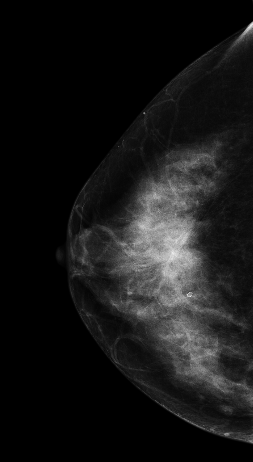

V-preview图像:

在常规2DMLO位图像上象限见一较大分叶状肿块影,但在CC位上没有发现明显肿块影像,在V-Preview(合成2D)图像上乳头后方似见不规则密度区,但仍不能明确病变位置,在DBT-plane我们可以乳晕后方清晰见一分叶状肿块影,肿块边缘呈放射状毛刺样改变,亦可见粗大血管影,可以明确肿块大小范围。

影像诊断:

右乳上象限肿块,考虑恶性,BI-RADS 5级。

右乳浸润性癌。